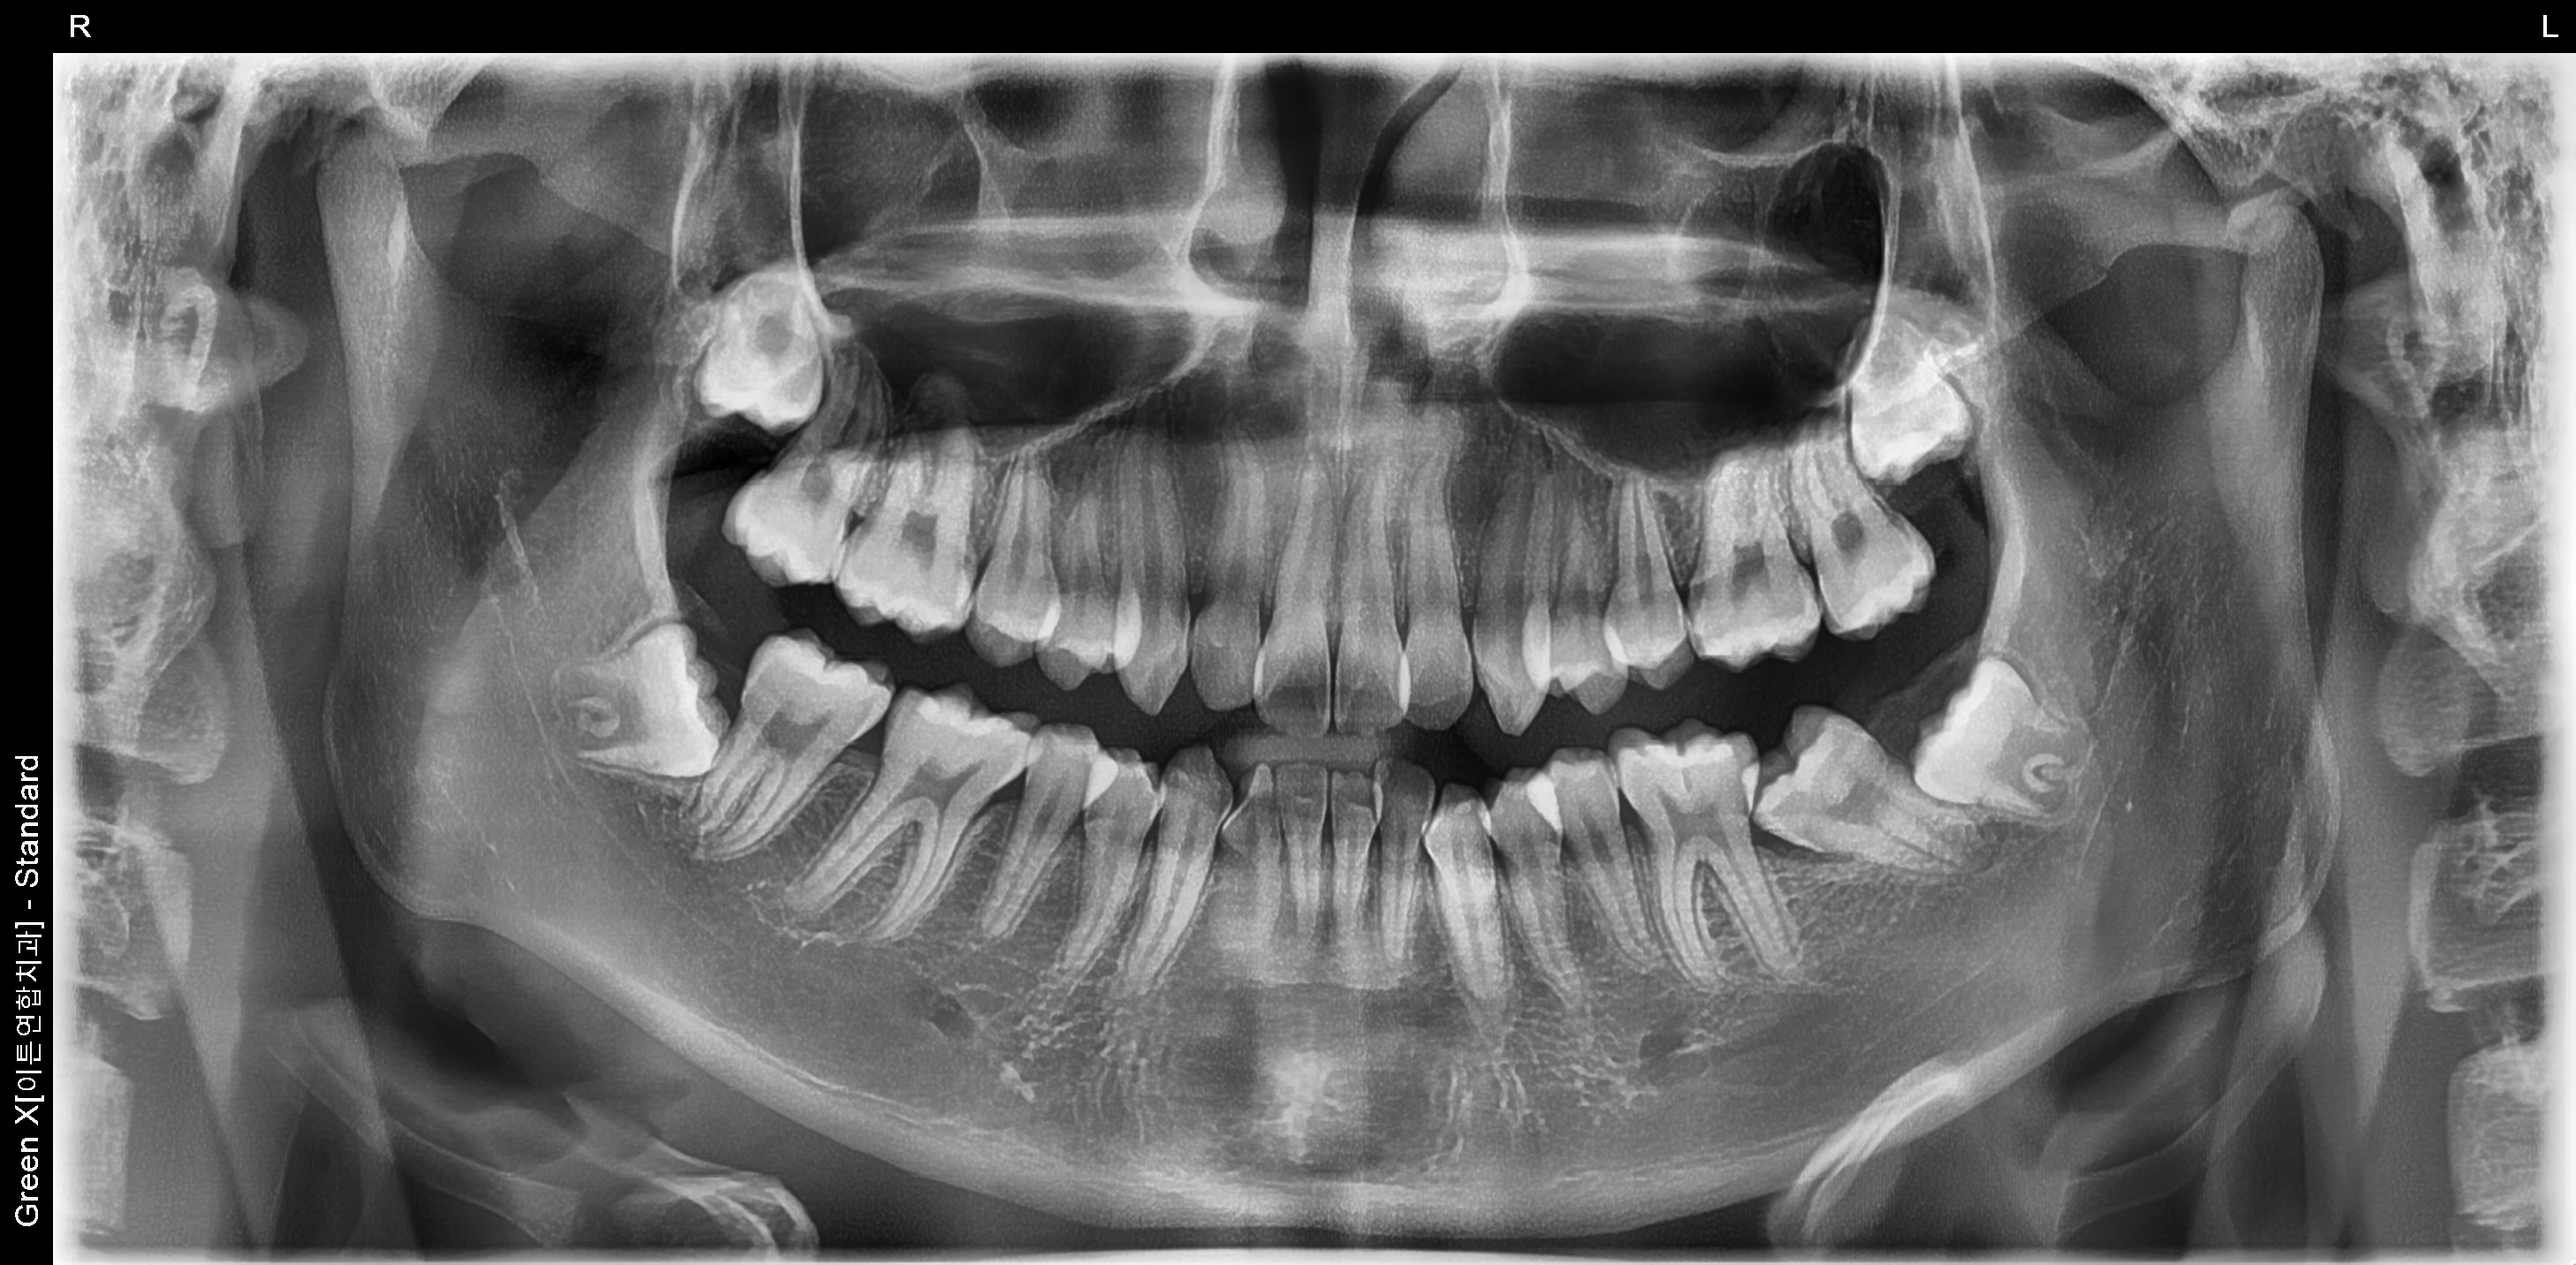

환자명 : 이OO

2025.05.26 업데이트

수술 후 촬영일자 : 2025.04.04

*해당 이미지는 의료법 제57조 동법 시행령을 준수하여 본원에서 직접 촬영했습니다.

치료 전후 사진은 환자분의 동의하에 동일 조건, 인물을 촬영 한 사진을 인위적인

수정 없이 사용해 일반적인 치과 치료 정보를 제공할 목적으로 게시되었습니다.

모든 시술은 개인에 따라 차이가 있을 수 있으며, 부작용이 발생할 수 있으니 의료진과

충분한 상담 후 진행하셔야 합니다.